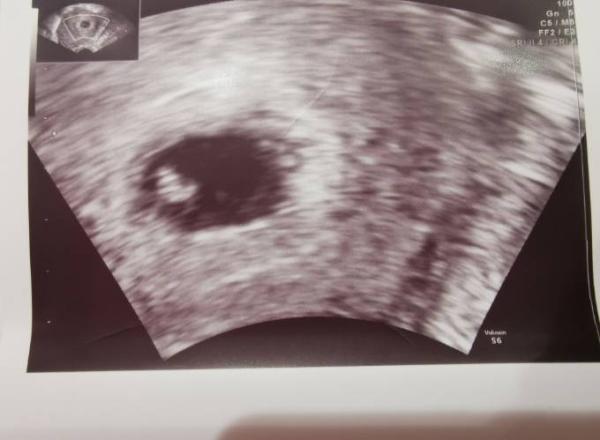

Mein Baby ist 4mm groß und das Herz schlägt kräftig ach das tat gut zu sehen, nachdem ich ja seit über einem Monat krank bin und von meinem Fa tatsächlich was verschrieben bekommen hab was bei halsweh und Husten und Heiserkeit hilft. Auch ein abschwellendes Kindernasenspray kann also nur besser werden! Nächster Termin ist leider erst am 7.1., wobei ich mich da schon freue ein ganzes, großes, richtiges Baby zu sehen :)

Bild zu 1. Frauenarzt Termin - Forum für Juli - Mamis